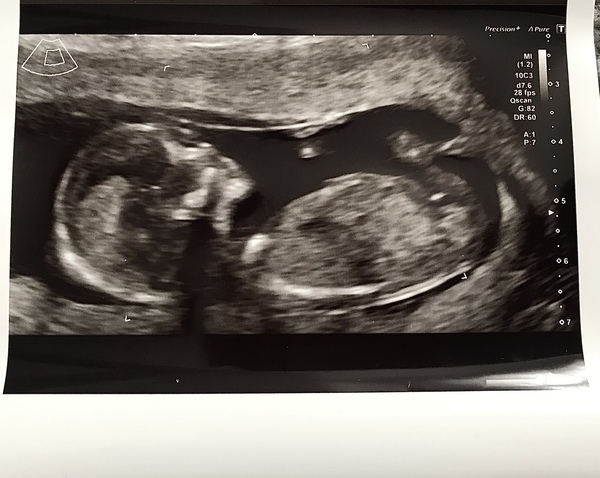

Just came back from my 12 week scan and I’m measuring 13w2d! Due date 13/4/22, here’s a picture ☺️

Little bubba was moving around, it felt so surreal. Got bloods down and measurements for the testing, so praying for the all clear.